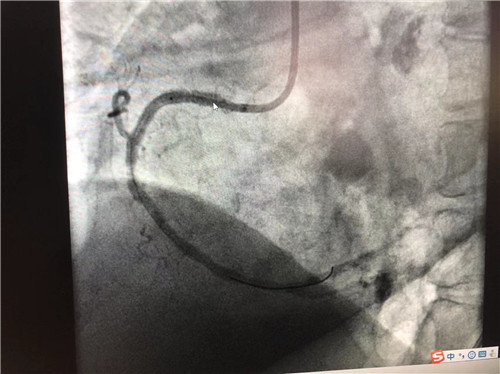

時間就是心肌,時間就是生命。導管室內,心血管內科副主任徐先進、主任助理農彥林已然待命,病人一到,團隊立即為其行深靜脈穿刺泵入血管活性藥物等,情況緩解后,行多體位冠狀動脈造影,確認RCA(右冠狀動脈)近端完全閉塞。經家屬同意,在汪念東院長的指導下,徐先進、農彥林、張星為患者行經皮冠狀動脈球囊擴張成形術+經外周靜脈穿刺中心靜脈置管術。術中,張奶奶再次出現室顫,心血管內科團隊臨危不亂,立即予以300焦電除顫搶救,患者竇性心律恢復。隨后,球囊擴張為其置入心臟支架,復查造影顯示血管恢復暢通,無明顯夾層,殘余狹窄不到10%。術后,張奶奶血壓偏低,轉入ICU無創(chuàng)呼吸監(jiān)護,2天后轉回心血管內科護理。

術后